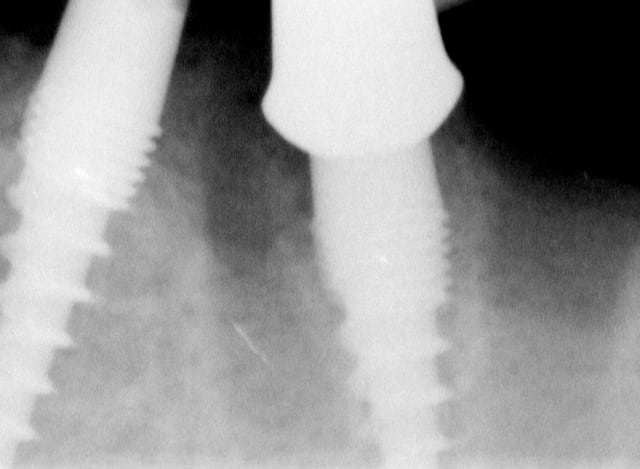

Bonjour flicflac je suis désolé de ma réponse tardive, oui il est vrai que ce n est pas beaucoup documenté ... je serai un menteur de dire que que je n ai jamais perdu des implants, surtout entre la 2eme et 8eme semaine après l implantation.Un échec vraiment à cause de la perte osseuse et avec le même process cela est arrivé une fois avec une madame, où l´os était encore infecté ( avant la chirurgie),mais après l ´échec (c était à la position 35) on a pu laisser le bridge. Malheureusement je n ai pas toutes les photos ici à Mallorque sur mon PC portable. Ci dessous une photo après 10 ans 46 47 et les implants au maxillaire.

Oui ca semble ....sur la opg radio tu peux voir la situation seulement deux semaines après l´implantation immédiate 34 jusqu´à 36 et 45, les derniers 2 photos montrent la même situation après un an ( où on a enlevé la supra construction pour un contrôle). Sur ce cas je voulais montrer la bonne régénération osseuse et de la gencive.